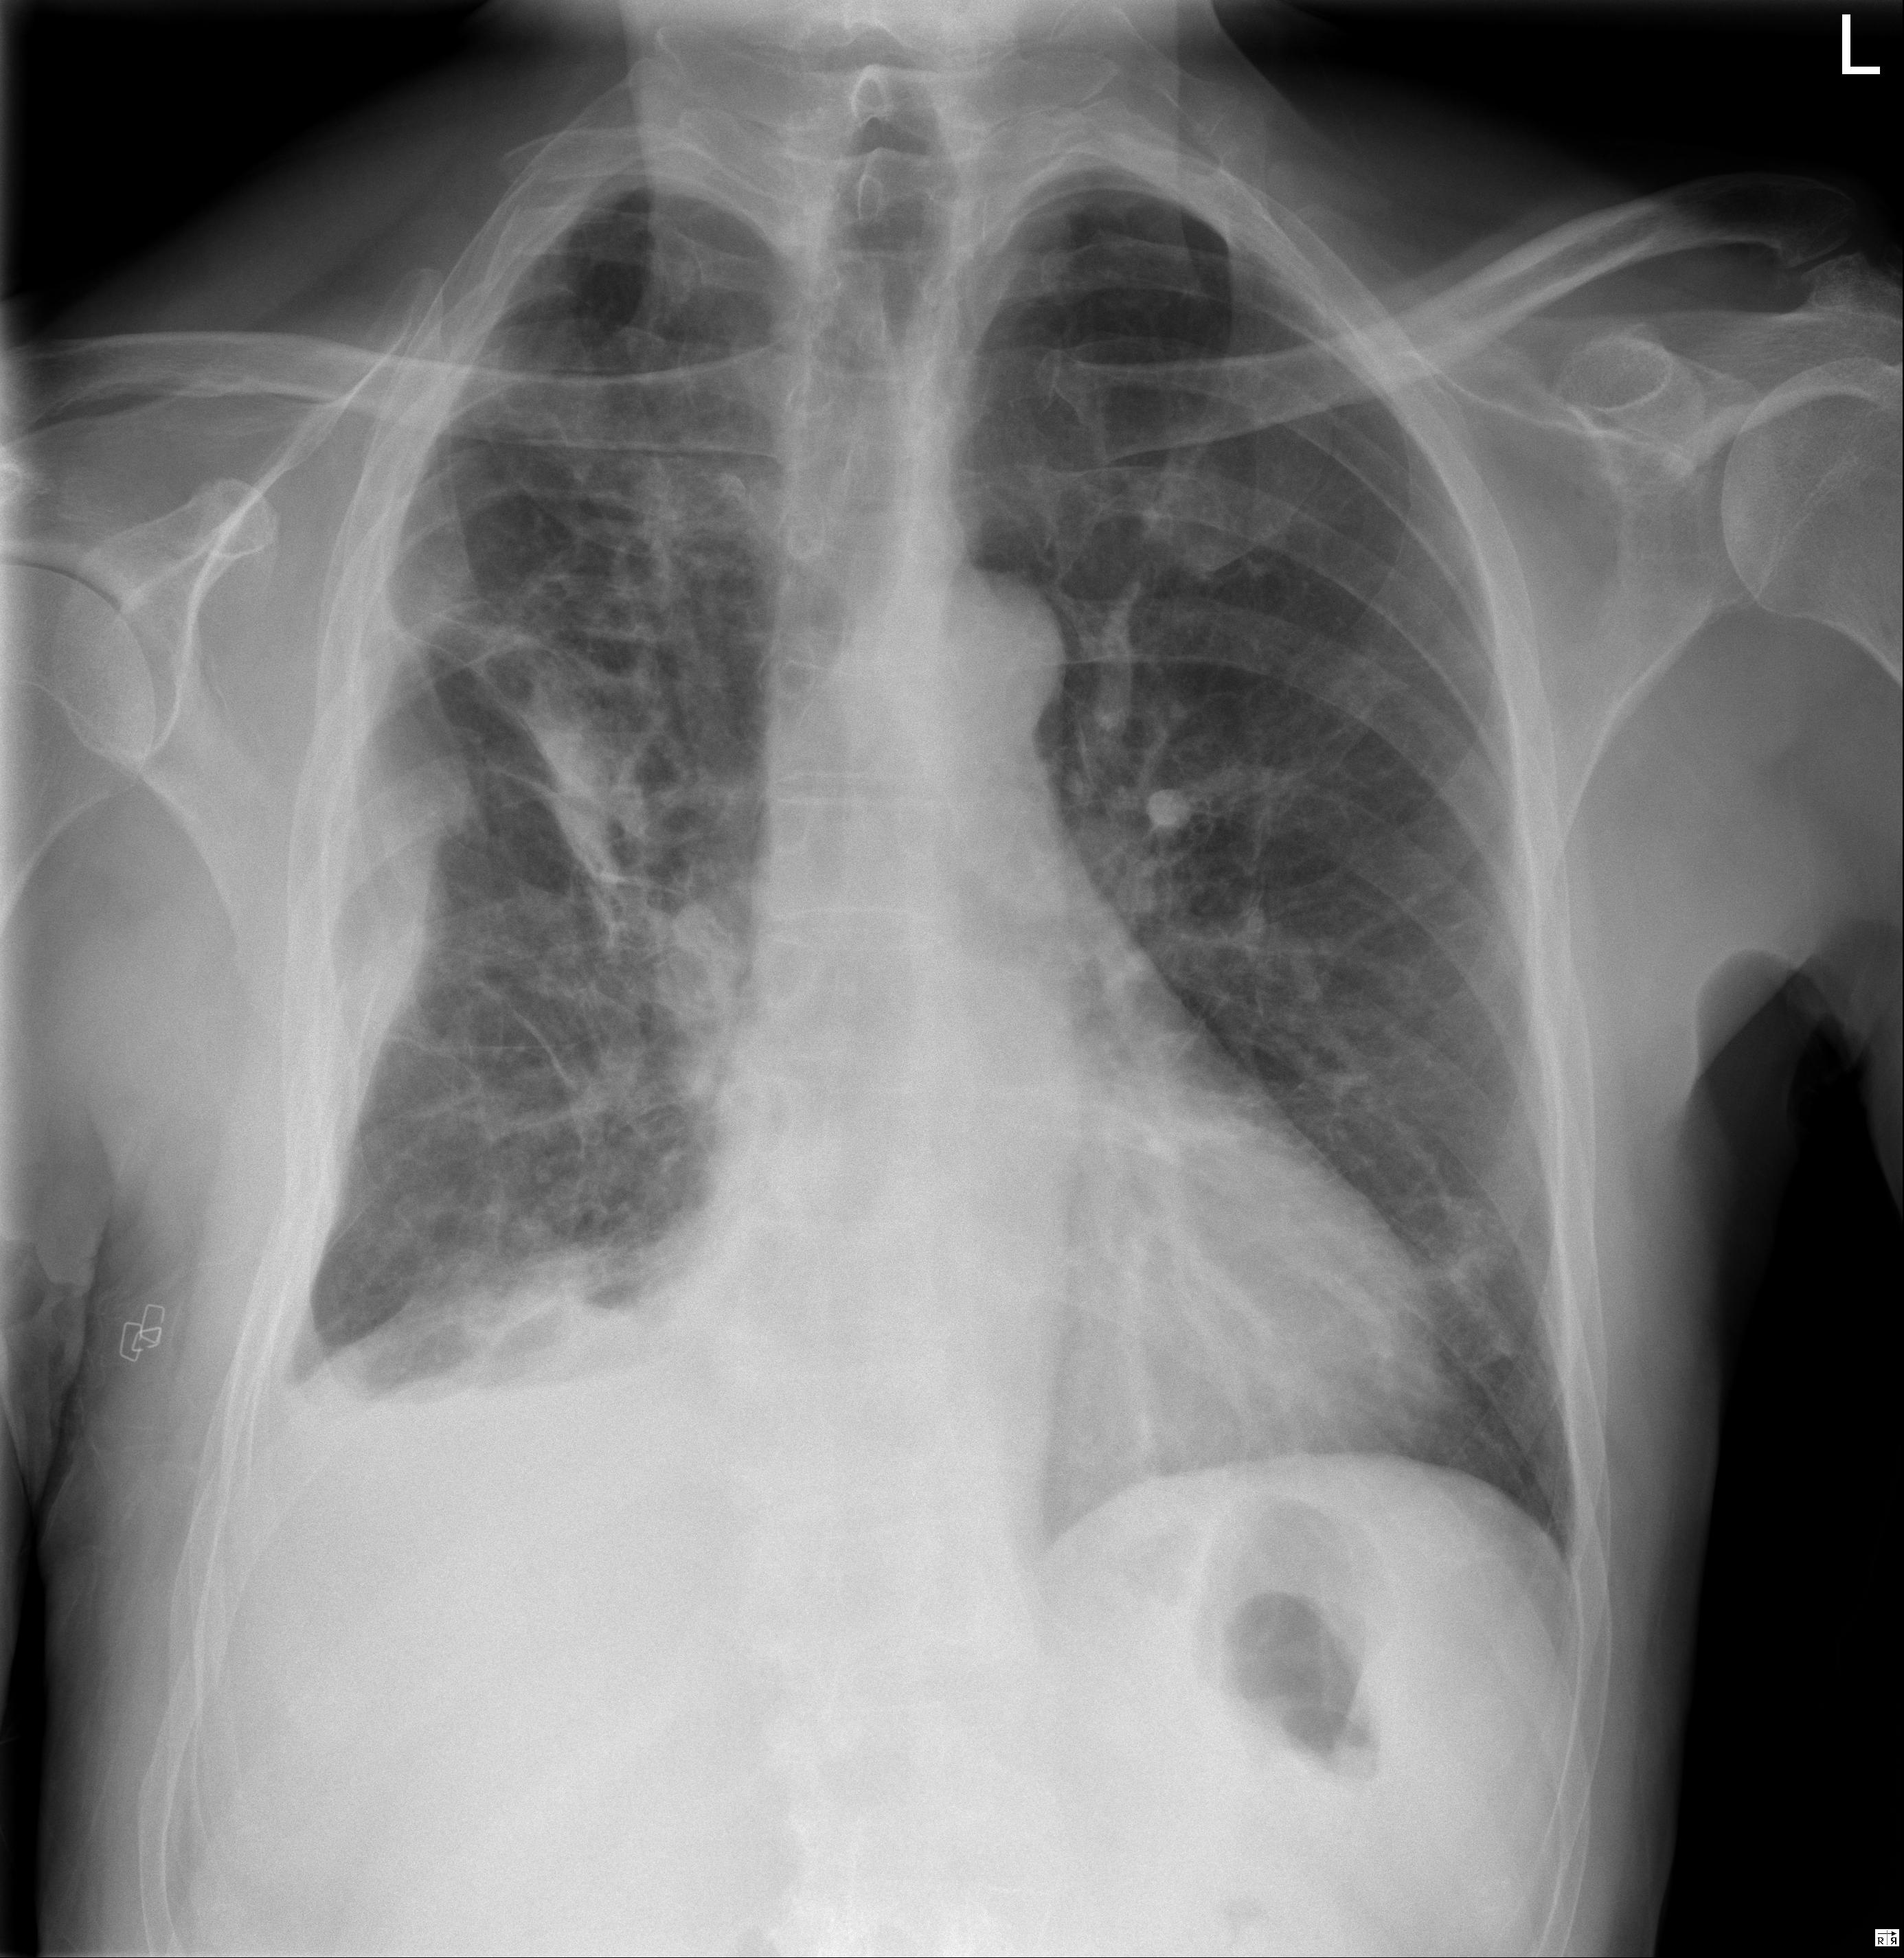

1 Tórax